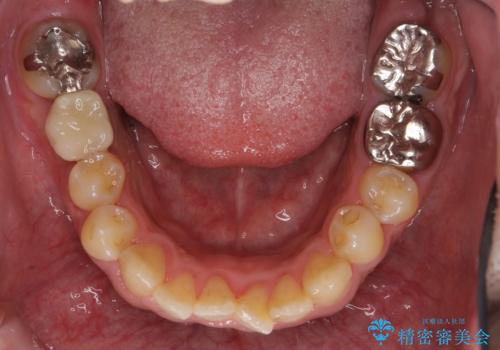

- 40代男性

- 右下の奥歯にインプラントを入れたいと来院。

抜歯から時間が経っており、骨が十分あったためすぐにインプラントを入れることが可能でした。骨も補う必要がありませんでした。

インプラントの術式は比較的単純で、難しくないですが、予後を見据えて角化歯肉を増やす手間をかけることが大変重要です。

インプラント手術時に同時に親知らずの抜歯も行い、腫れや痛みなどを1度で終わらせるようにしました。